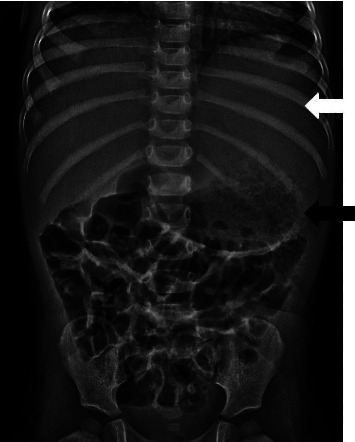

Congenital hepatic fibrosis is a rare, autosomal recessive, fibro-polycystic disease resulting from ductal plate malformation, leading to proliferation and fibrosis of bile ducts. Progressive hepatic fibrosis leads to portal hypertension and varices which can present with life threatening gastrointestinal hemorrhage. We report a case of congenital hepatic fibrosis in a 2-year-old child who presented with 8 days of fever without any significant medical history or physical examination findings.